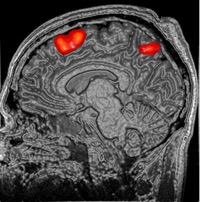

While significant advancements in artificial intelligence (AI) have catalyzed progress across various domains, its full potential in understanding visual perception remains underexplored. We propose an artificial neural network dubbed VISION, an acronym for "Visual Interface System for Imaging Output of Neural activity," to mimic the human brain and show how it can foster neuroscientific inquiries. Using visual and contextual inputs, this multimodal model predicts the brain's functional magnetic resonance imaging (fMRI) scan response to natural images. VISION successfully predicts human hemodynamic responses as fMRI voxel values to visual inputs with an accuracy exceeding state-of-the-art performance by 45%. We further probe the trained networks to reveal representational biases in different visual areas, generate experimentally testable hypotheses, and formulate an interpretable metric to associate these hypotheses with cortical functions. With both a model and evaluation metric, the cost and time burdens associated with designing and implementing functional analysis on the visual cortex could be reduced. Our work suggests that the evolution of computational models may shed light on our fundamental understanding of the visual cortex and provide a viable approach toward reliable brain-machine interfaces.